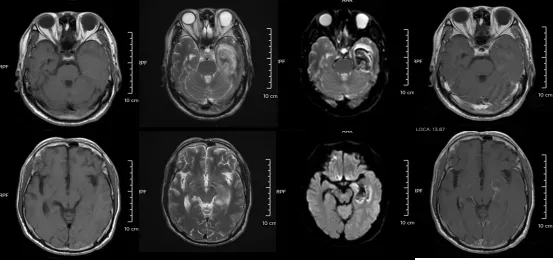

某单纯疱疹病毒性脑炎患者的医学影像。图源:浙江大学医学院附属第二医院

但如果拖延治疗,甚至会引发脑炎,可能出现癫痫、肢体偏瘫、尿潴留、认知功能障碍等严重后遗症,恢复时间长达3-6个月,甚至影响终身。